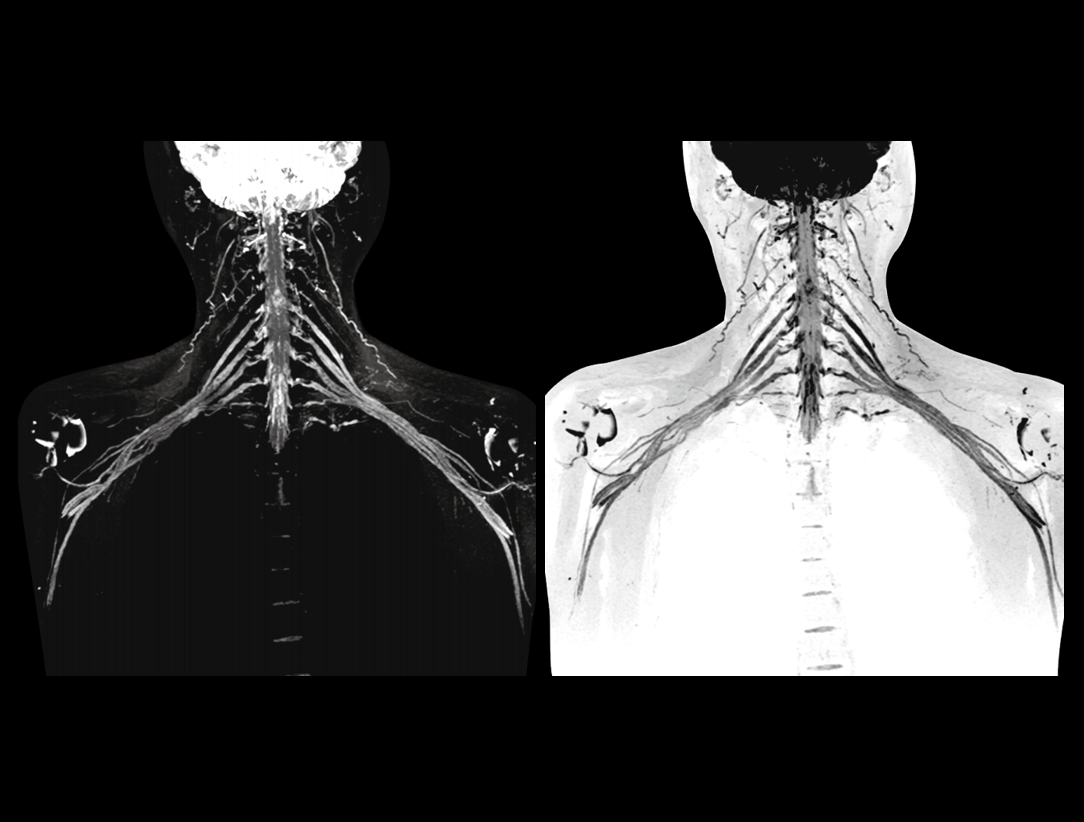

32/48 kanałów RF doskonale uzupełnia nasze zintegrowane cewki o dużej gęstości, dając znaczny wzrost stosunku sygnału do szumu obrazu.

Potężny magnes 3,0 T ma krótką konstrukcję (170 cm), aby zapewnić wysoką jednorodność pola magnetycznego. Daje to solidne podstawy szybkiego obrazowania i doskonałego nasycenia tłuszczu w dużym polu widzenia, a także znakomitego obrazowania poza centrum.